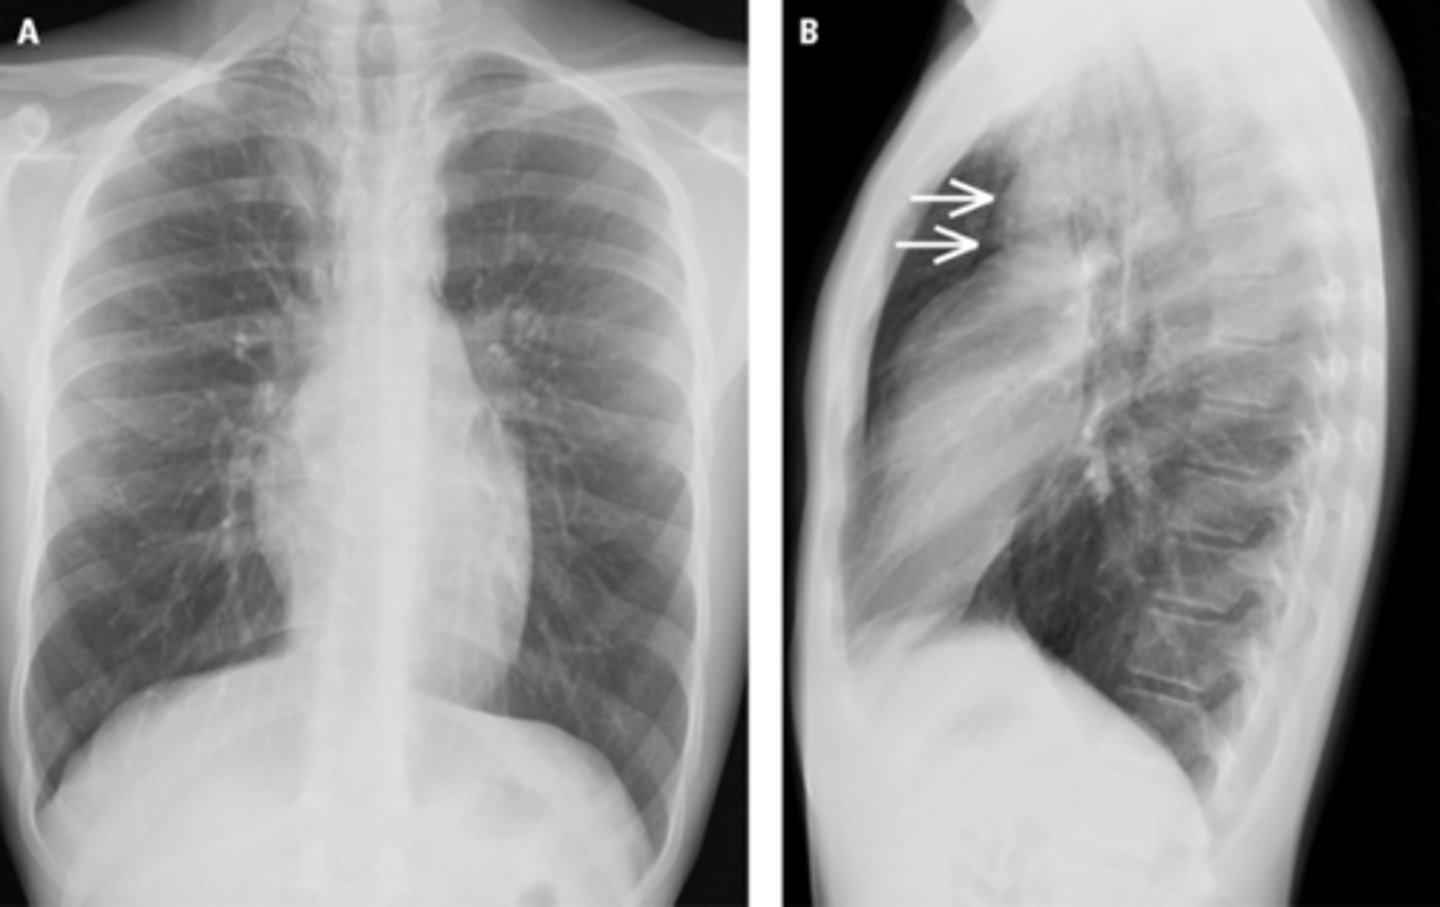

Air in the pleural space that causes collapse of the lung usually seen in the apices if pt is upright

Pneumothorax

Pneumothorax (apices)

Pneumothorax (moderate, non tension)